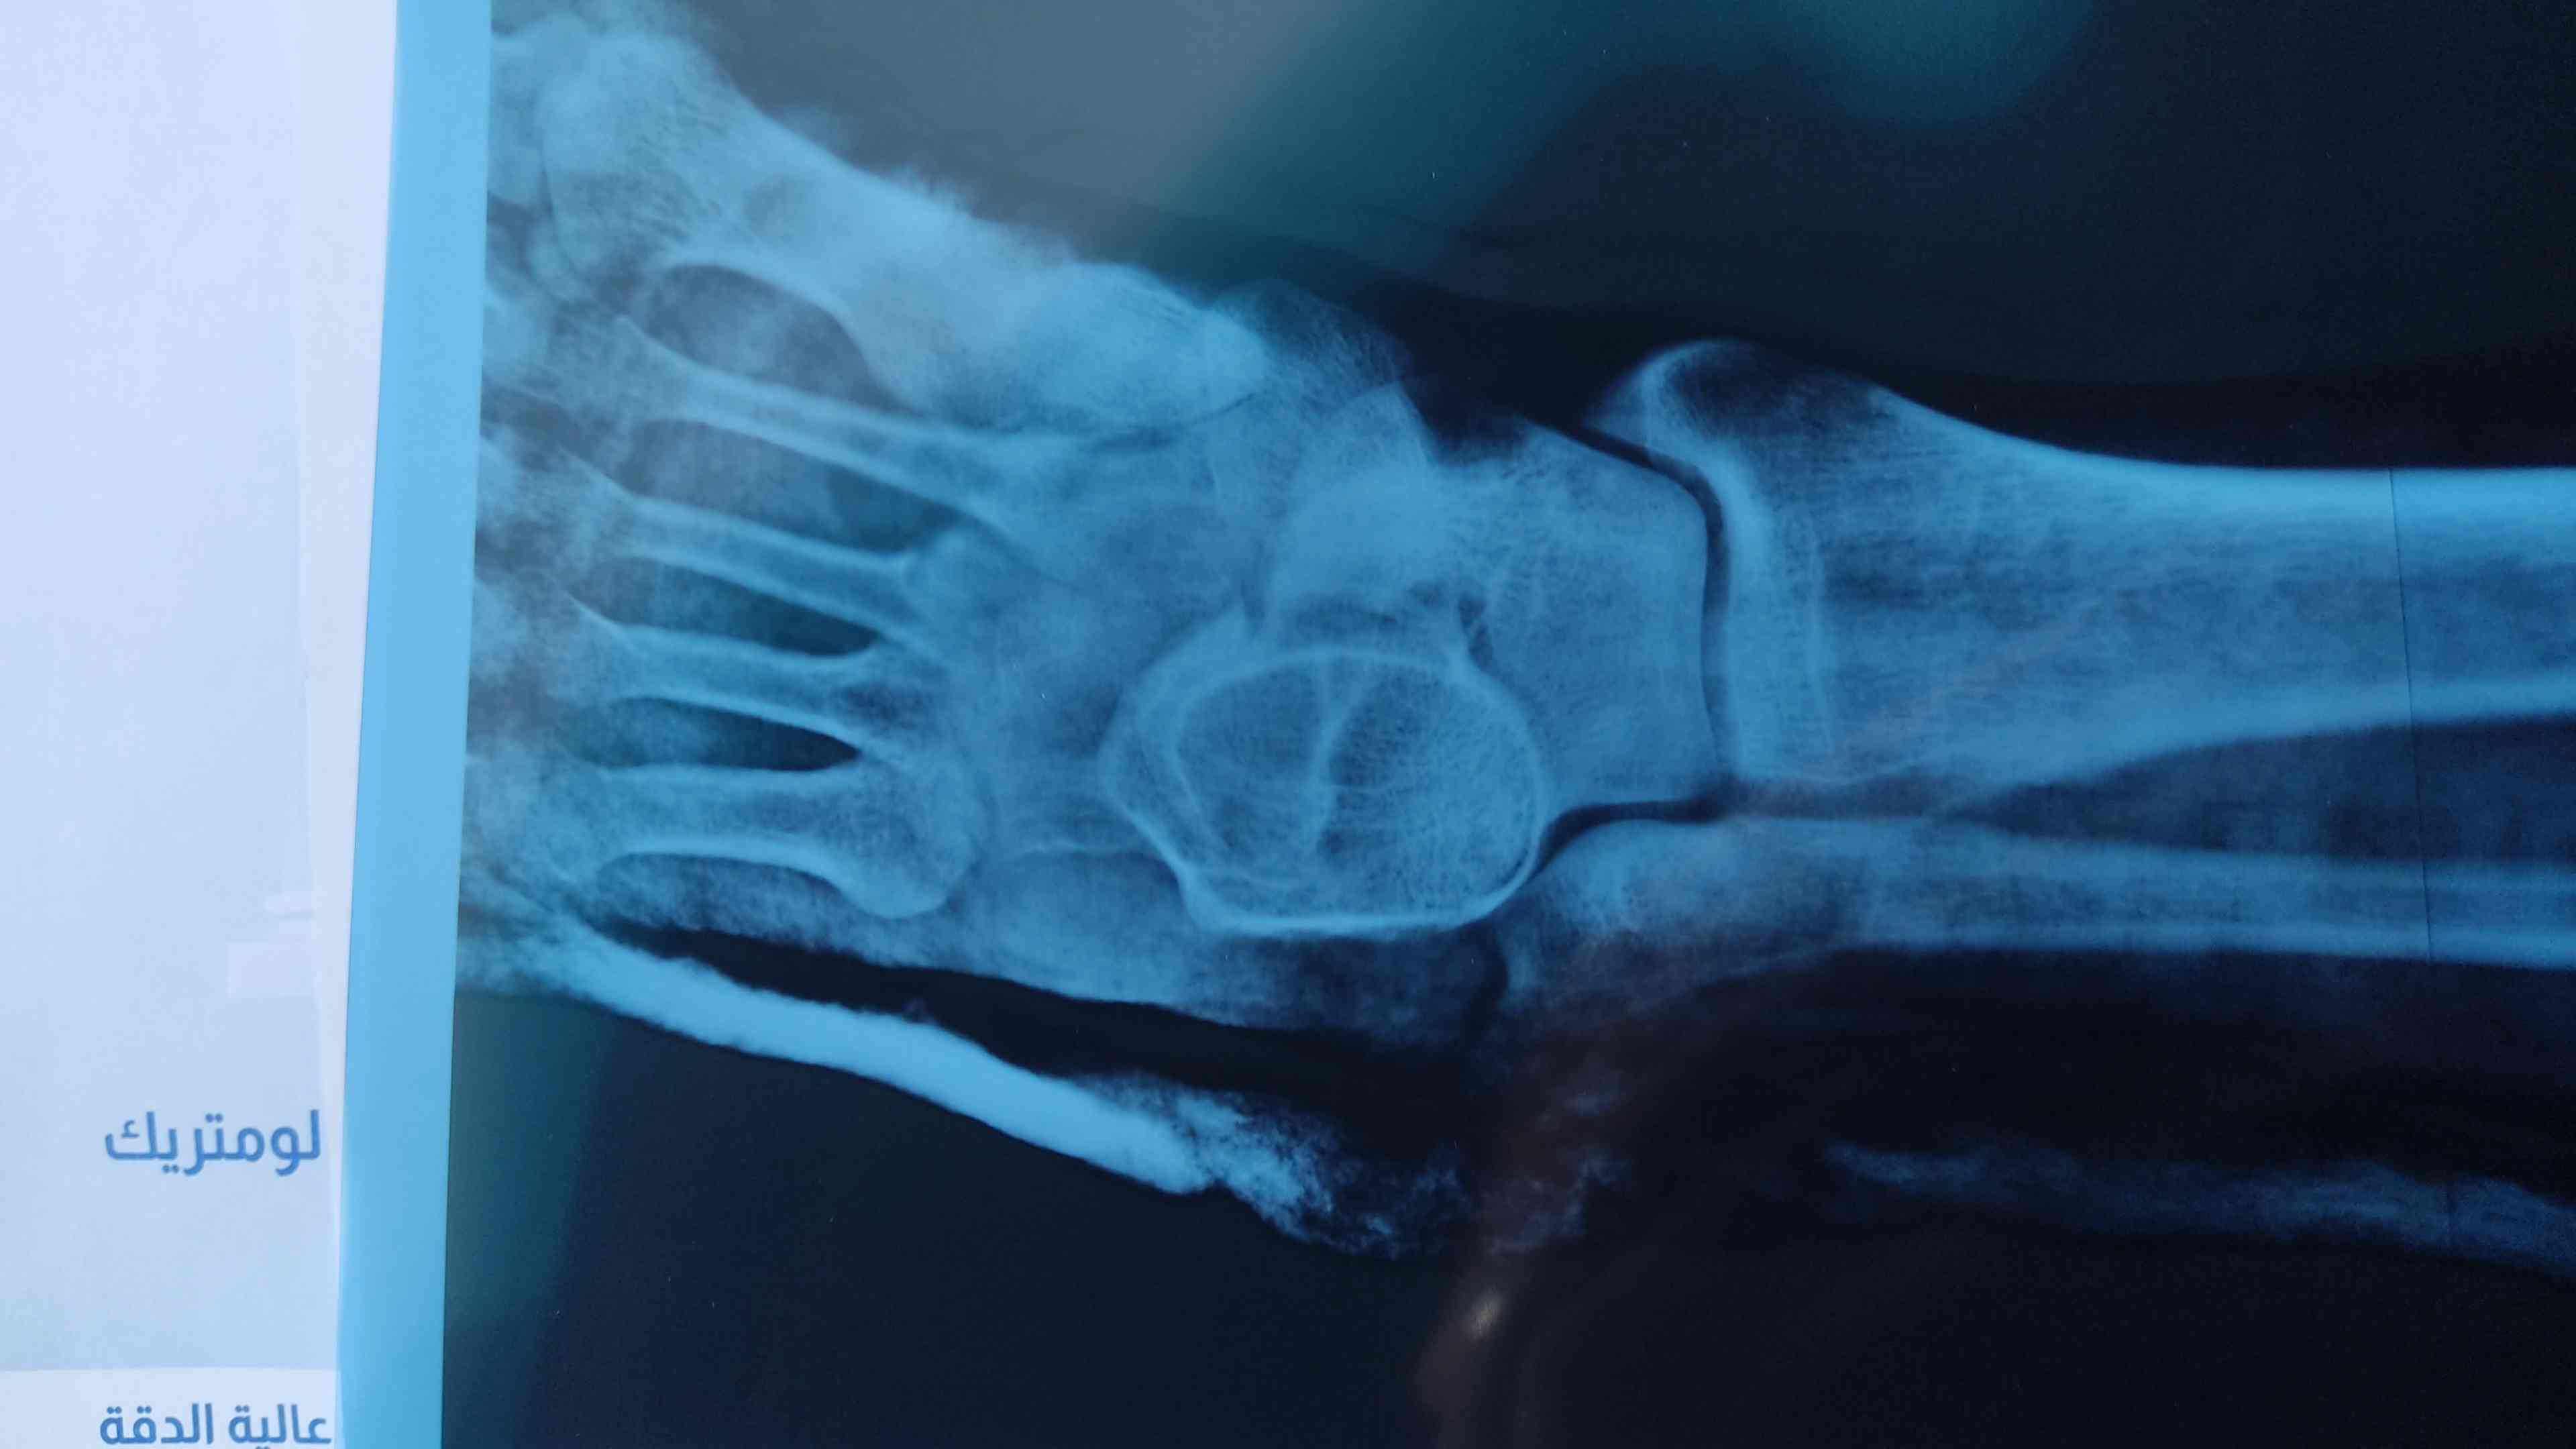

مرحبا قدمي إلتوت تحتي ووقعت مع الم شديد ذهبت للدكتور وصورت شعاعي فقال هناك كسر ليس متبدل وليس هناك ورم لكن يوجد بروز لعظمة الكاحل ذهبت لدكتور اخر قال لايوجد كسر